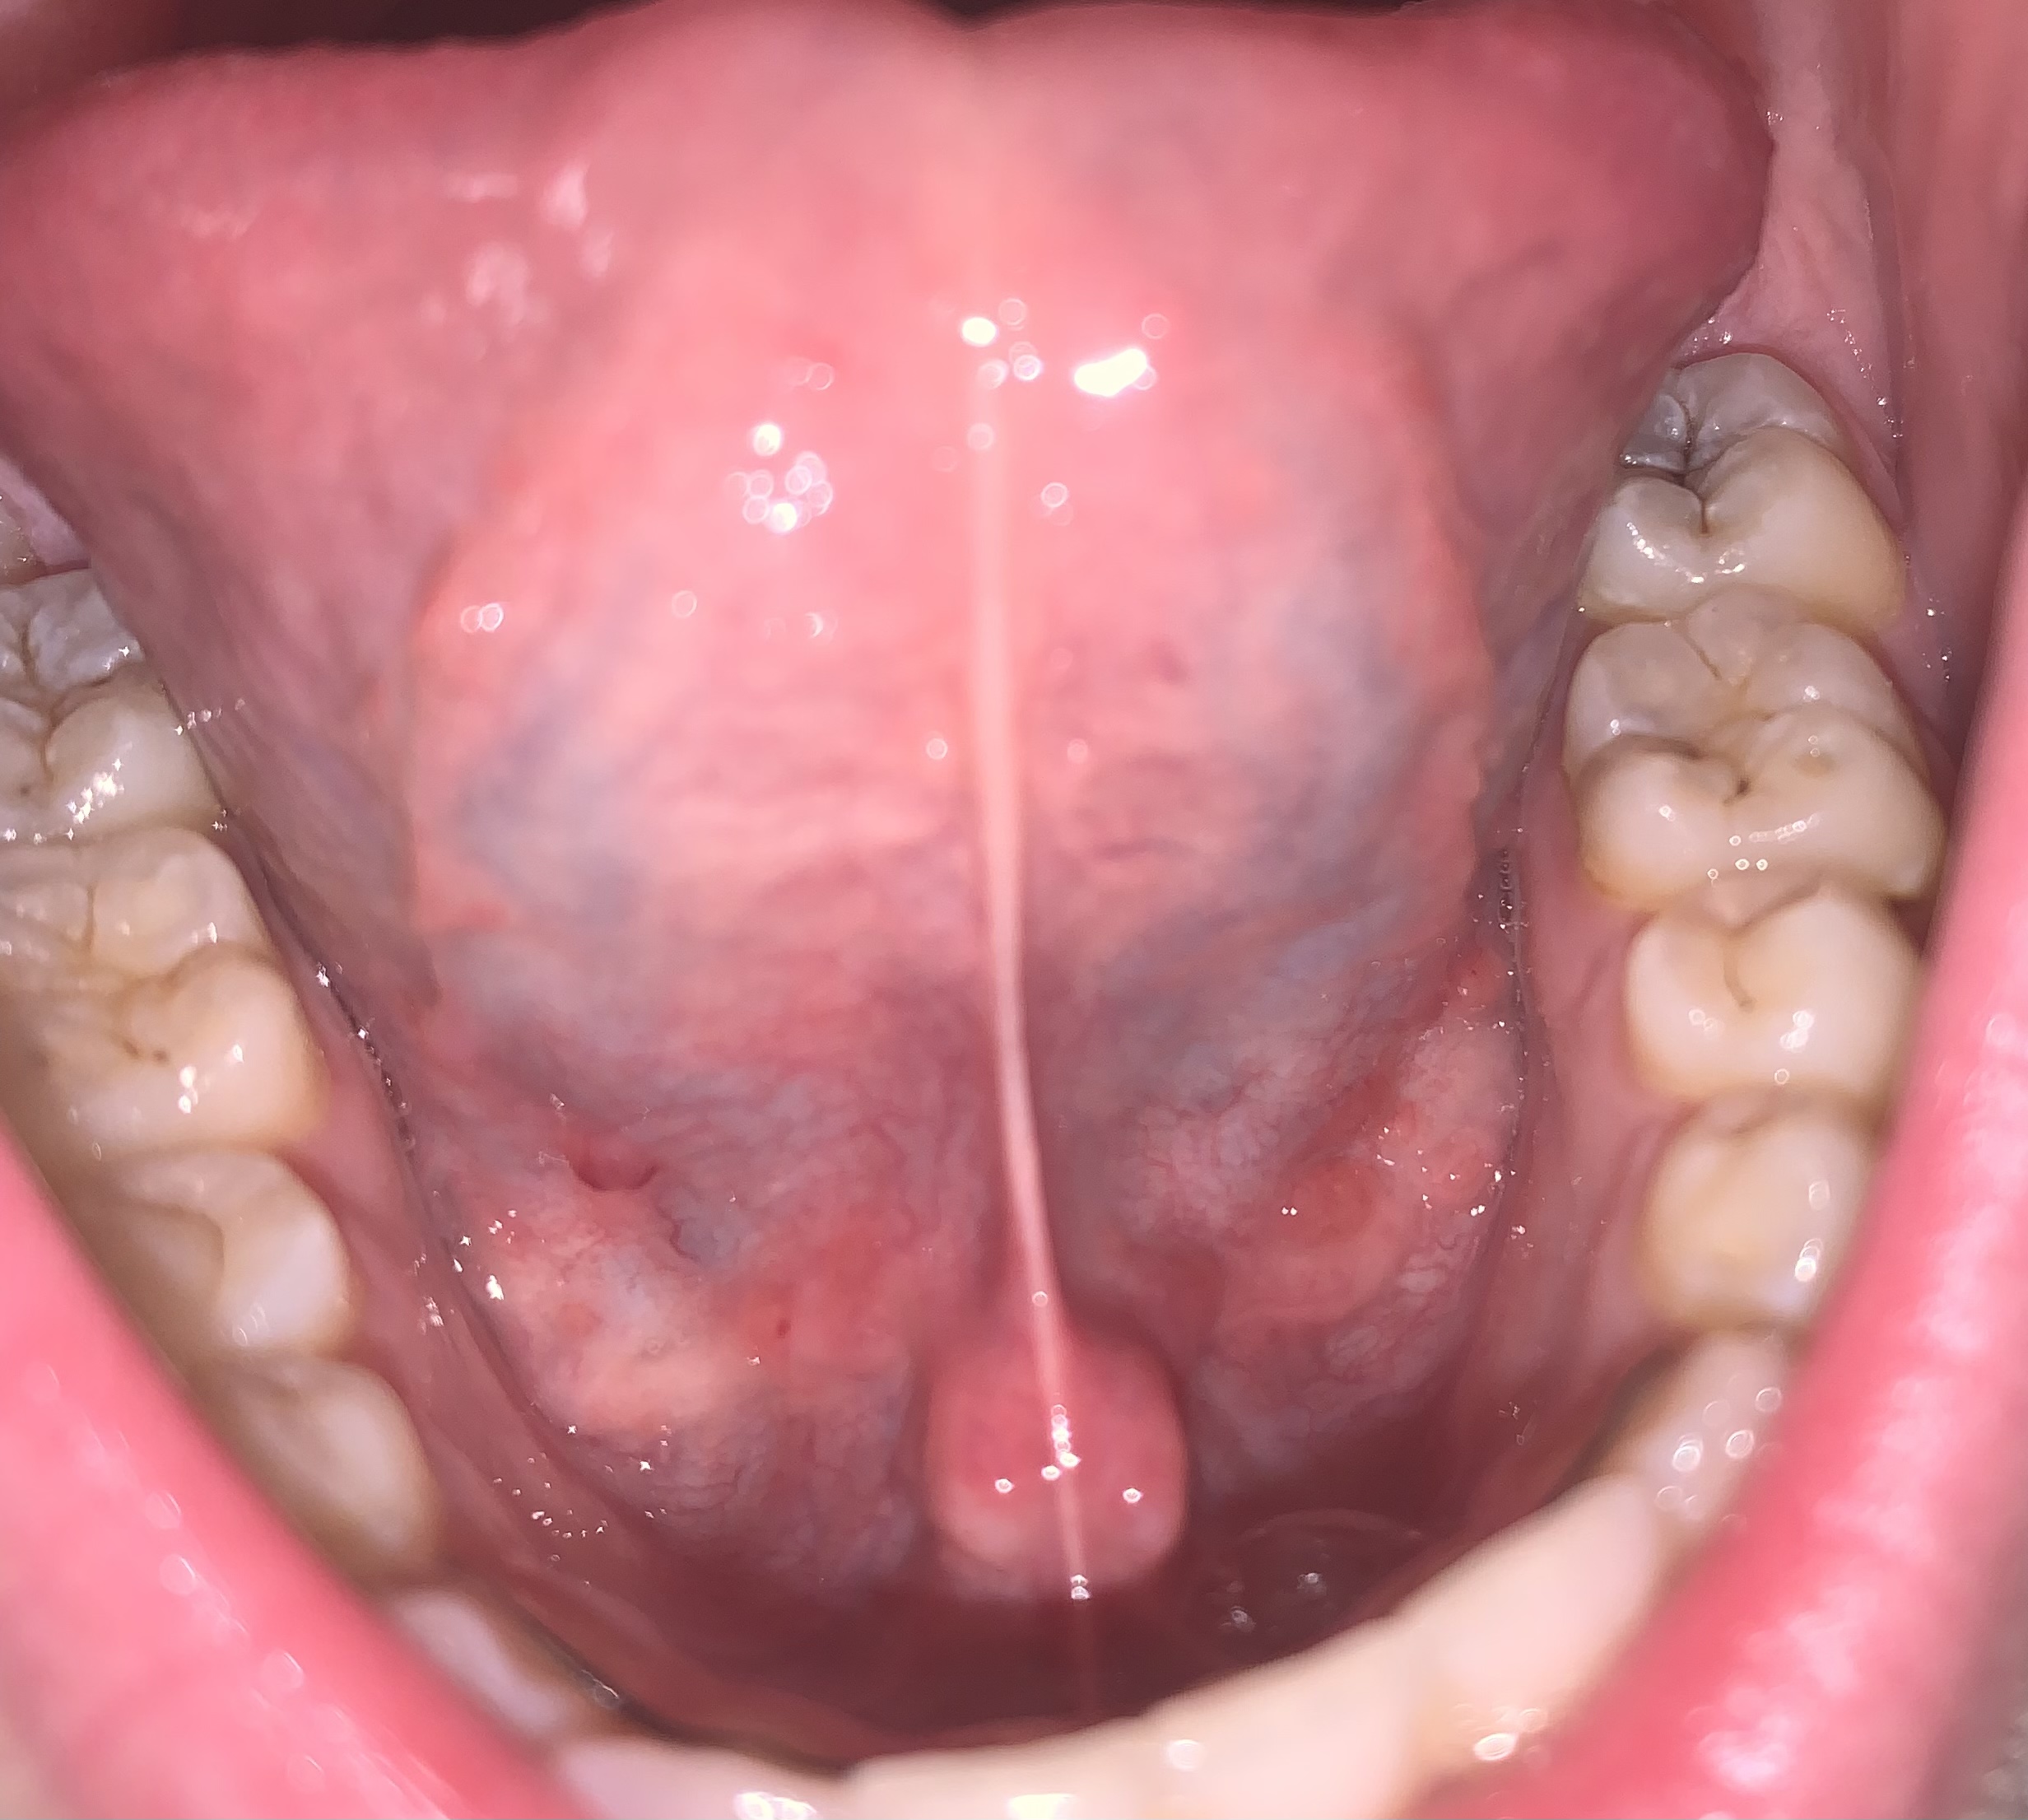

Dit is een foto van hoe het…

Zoals te zien, zijn er nog wel rode blaasjes en de twee ‘draden’/‘lijnen’ die via mijn tong omhoog lopen. Over Het laatst genoemde weet ik niet of het normaal is of niet, maar het viel mij op. Wat denkt u ervan?

Foto*